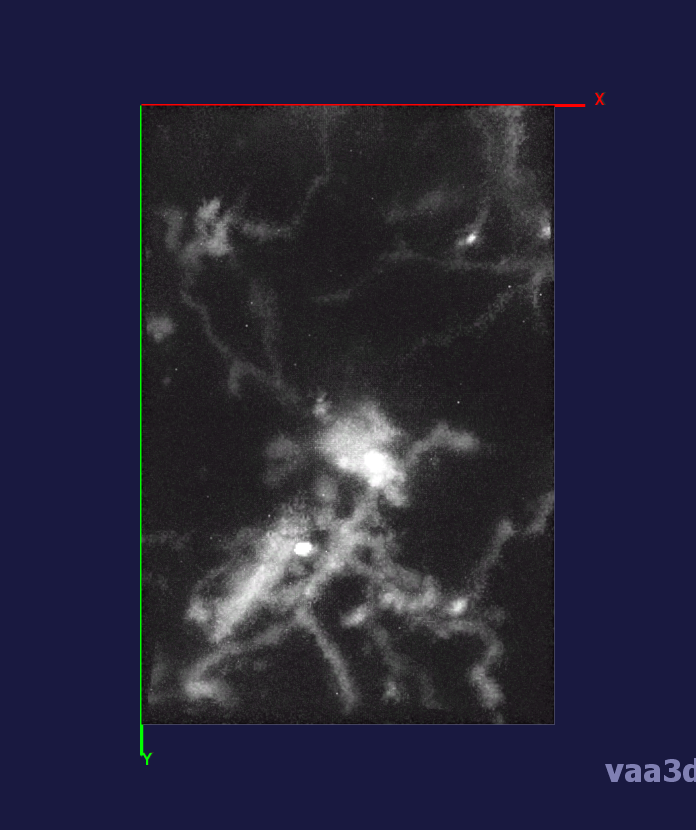

The 3D movies of microglia were imaged over 20 minutes with z-stacks taken at one minute intervals, containing single or multiple microglia per field of view. Some of the images were cropped from a larger field of view containing about 10 different cells and two images were imaged from a zoomed in view of one individual cell. The images ranged from a horizontal pixel width of .01 um and a vertical pixel width of .01 um to horizontal pixel width of .2 um and a vertical pixel width of .2 um. In the 3D images, there is variation in intensity contrast throughout the cell, non-structural noise, and fluorescence bleeding through z-stack due to the lengthy imaging technique which makes it difficult to visualize and process. The images were pre-processed using histogram equalization which increased the intensity throughout the cell but further increased noise in the background.

In our experiments, we compare the coupled TuFF-BFF microglia segmentation results with those given by L2S [21] and the Chan-Vese segmentation method [22]. The groundtruth in 3D was attained by manually tracing the object slice by slice from the z-stack. It must be noted that this was done by eye and could have some error. Figure 2 shows the visual comparison of the segmentation results for our dataset. Our result shown on the third column captures both the soma and processes. Figure 3 shows the Dice coefficient comparison of each segmentation method to the ground truth. Since the soma is much larger than the fine processes in the microglia, the processes have less volumetric impact on the similarity score. As explained in Section 1, segmenting the processes is important for quantifying the extension from the soma and its volume of surveillance. We use the Dice coefficient to quantitatively compare the ramification by taking the convex hull of the resulting segmentation. The Dice coefficient is a similarity measure that is computed using with where is the ground truth and is the compared image.